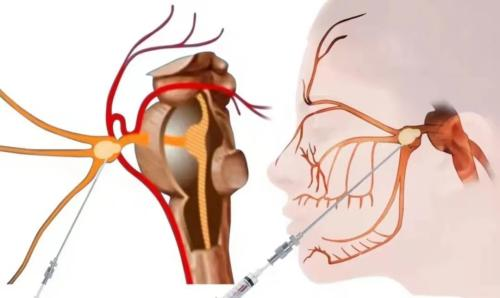

近日我院疼痛科成功开展一例经皮三叉神经半月节球囊压迫术,为一位82岁高龄患者治疗困扰多年的三叉神经痛。患者受三叉神经痛折磨2年多,院外经药物等治疗疼痛控制差,吃东西、说话、刷牙疼痛严重,严重影响日常生活和睡眠,来到我院疼痛科。完善相关检查后,诊断原发性三叉神经痛,累及右侧第2、3支,经过疼痛科专家们研讨,决定行经皮三叉神经半月节球囊压迫术,手术时间10多分钟,术后患者疼痛立刻缓解,3天后顺利出院。

经皮三叉神经半月节球囊压迫术是一种微创技术,是目前疼痛科治疗三叉神经痛有效方法之一,优点:创伤小,手术时间短,术后疼痛立刻消失,恢复快,住院时间短。

经皮三叉半月神经节球囊压迫术

经过面部口角处穿刺到三叉神经半月节内,放入球囊,向球囊里打入对比剂,使球囊扩张,完美显示一个“梨”形,压迫3-5分钟,压迫毁损感觉神经,保留运动神经,阻断疼痛信号传导,达到止痛目的。适合单支或多支发病患者,尤其高龄、合并症多,不愿意接受开颅手术患者。术后面部稍有麻木。